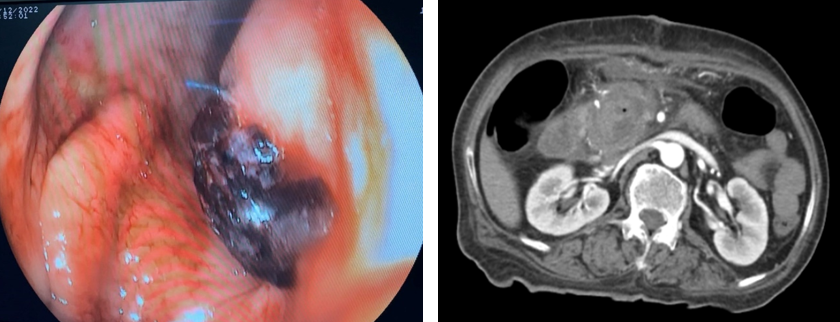

- Đến 8h ngày 27/12:  bệnh nhân lại nôn ra máu tươi, huyết áp dao động 80/40 – 90/50, mạch 120 lần/phút. Bệnh nhân được chỉ định chụp mạch tạng (DSA). Kết quả chụp mạch có 1 túi giả phình nằm ở 1 nhánh của động mạch vị tá tràng đang chảy máu. Bệnh nhân được can thiệp nút túi giả phình này. Sau can thiệp bệnh ổn đinh, theo dõi đên ngày 03/01/2023 bệnh nhân huyết động ổn, không nôn, ăn uống được, xét nghiệm công thức máu ổn. Bệnh nhân được ra viện cùng ngày, sau ra viện ổn.

Hình 7 và 8.  Chụp mạch sau can thiệp